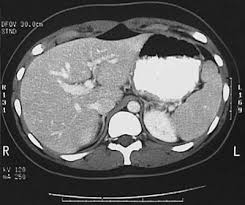

Karena jantungmerupakan organ yang bergerak cepat satu-satunya cara untuk mengambil gambar adalah jika kita dapat memindai gambar secepat denyut jantung atau mendekati. This is a CT of the Abdomen and Pelvis Enterography protocol. Berdasarkan tujuan dan manfaatnya beragam jenis CT Scan mulai dikembangkan antara lain.

Mamografi Tanyakan Harga Lihat harga bandingkan hasil. Various problems related to the gallbladder pancreas and kidney. This is a higher quality study than a standard CT.

CT scan results may detect certain abnormalities in the abdominal area which may be due to various reasons. Pembayaran mudah pengiriman cepat bisa cicil 0.